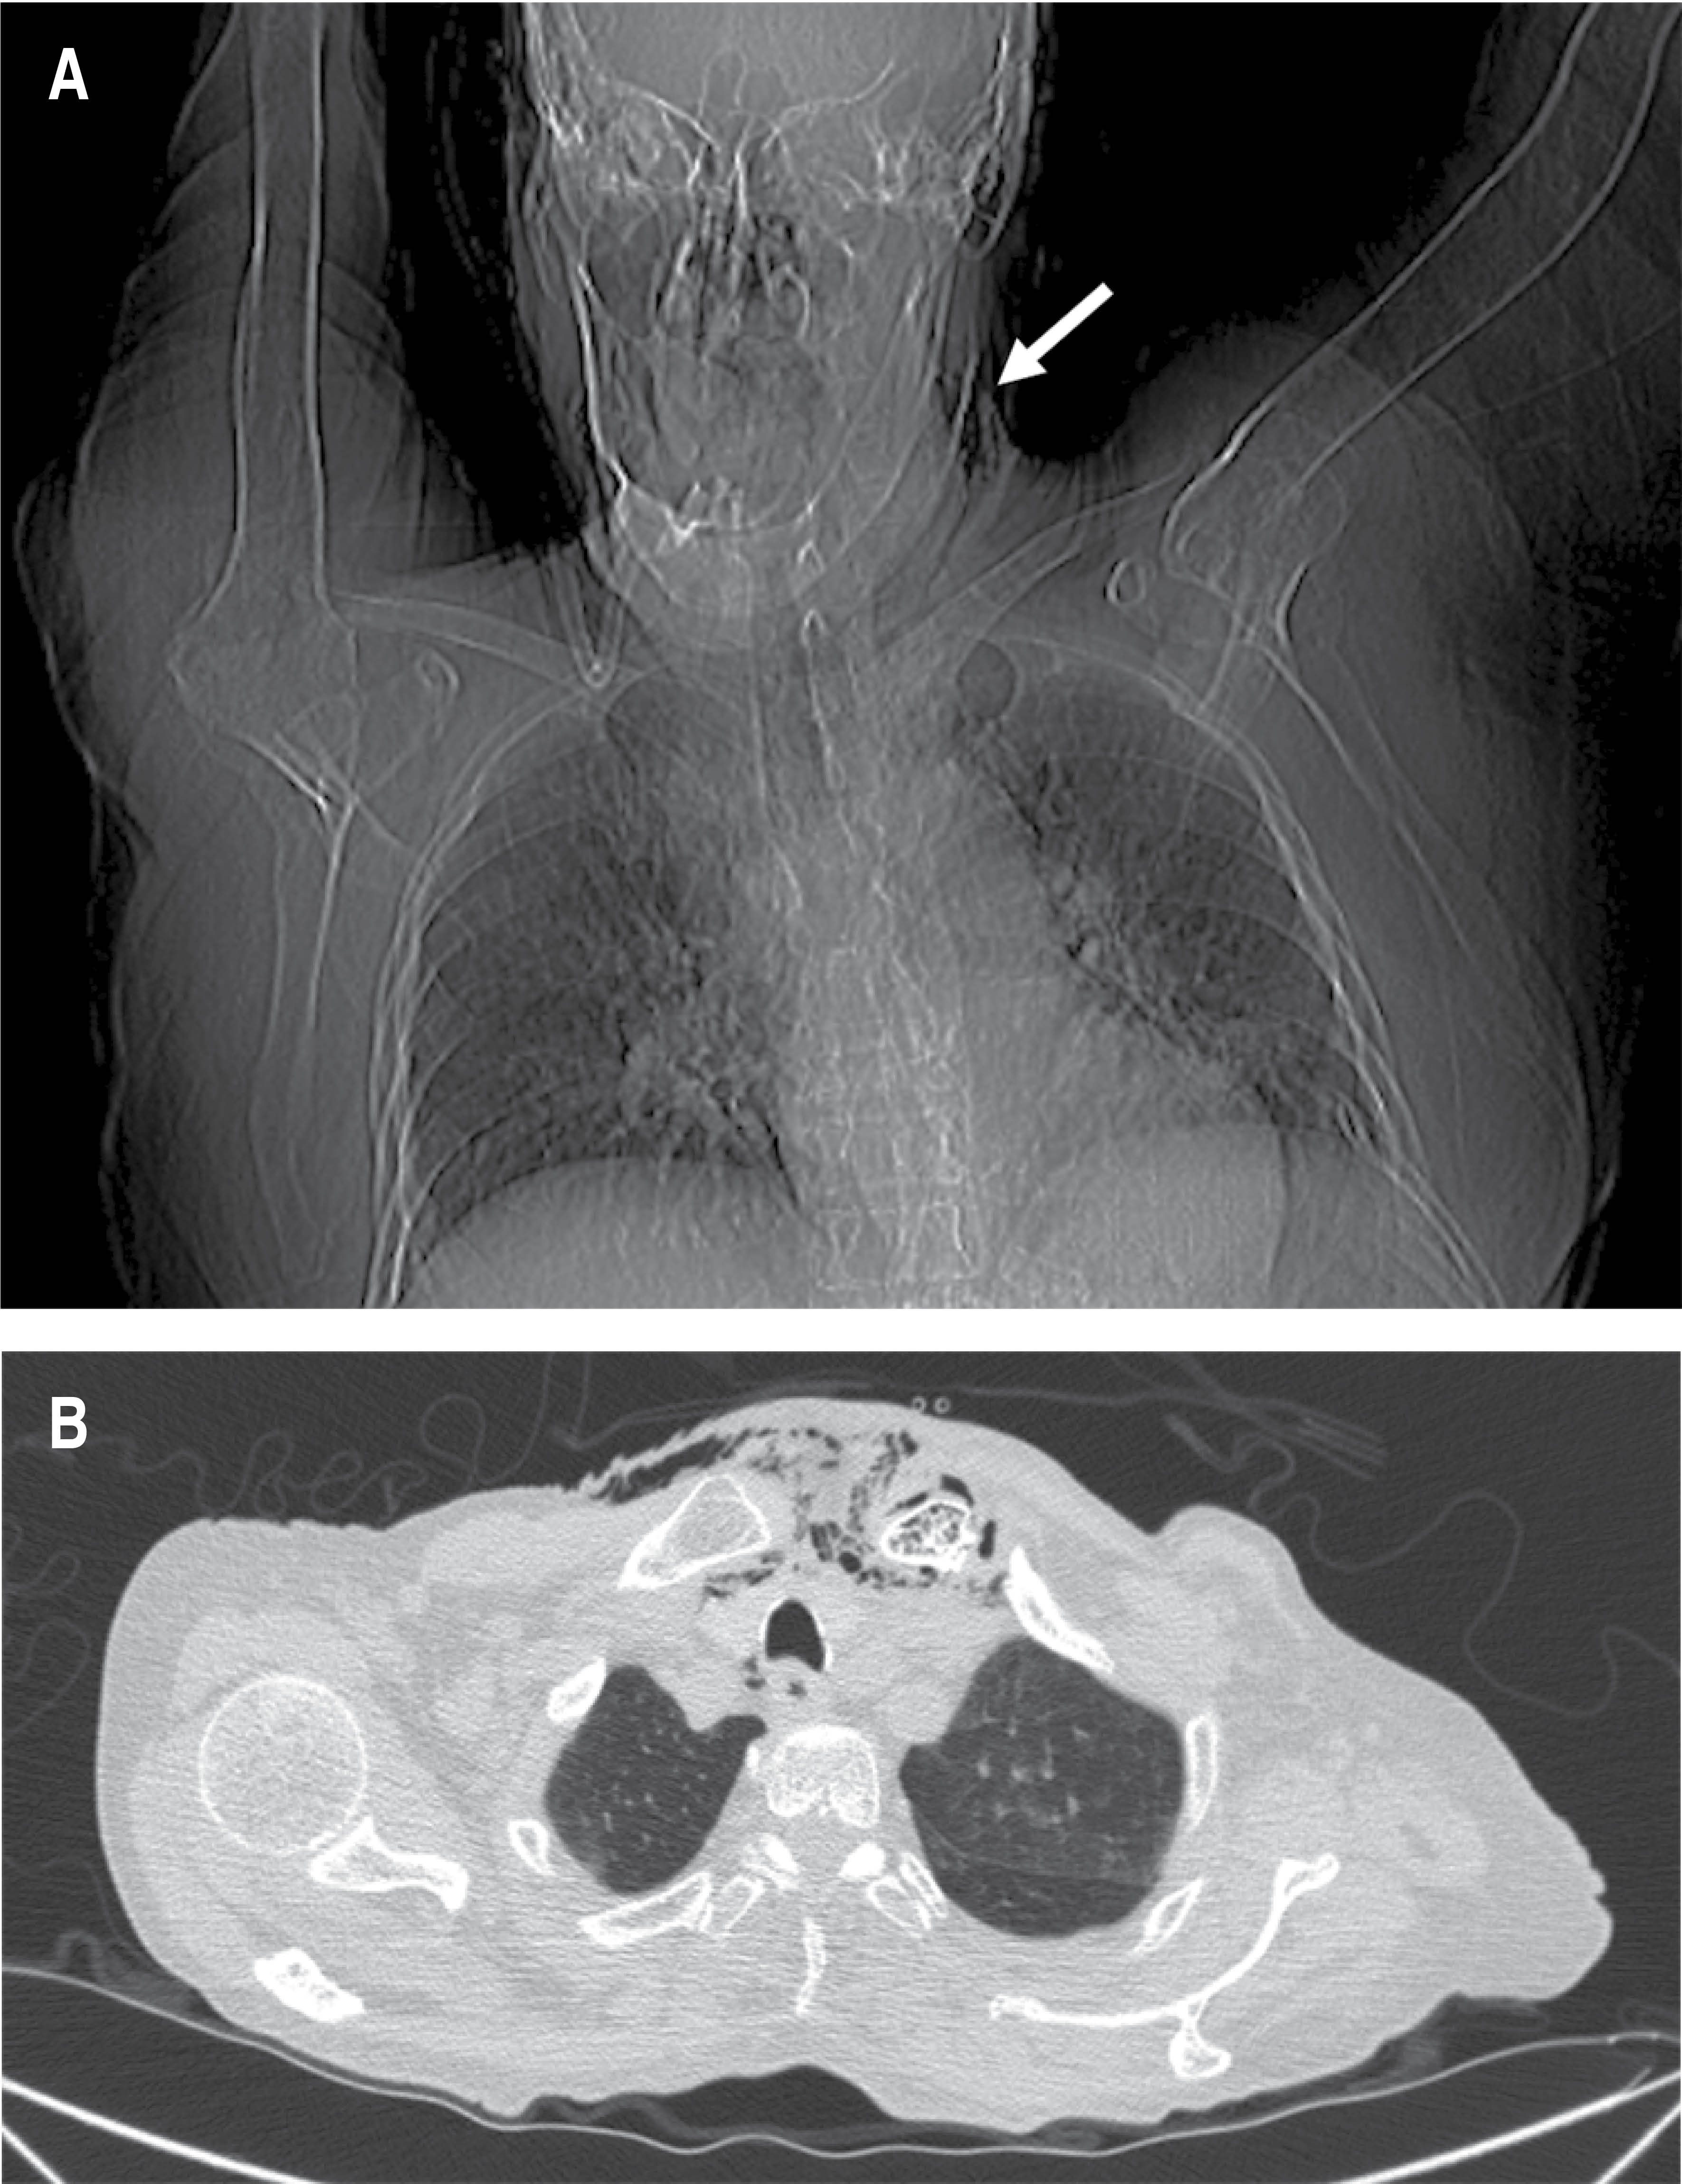

During the initial approach in the emergency department, it was decided to place a urinary catheter (the patient still had spontaneous diuresis), with evidence of pyuria; an attempt was made to place a central venous access, palpating the presence of subcutaneous emphysema, so it was requested to perform a computed tomography scan; with report of an inflammatory process located in the cervical region with extension to the upper mediastinum, as well as the presence of intramedullary gas in the left clavicle and sternal manubrium, suggestive of osteomyelitis (Figures 1 and 2). The study of the peritoneal fluid obtained through the dialysis catheter was found to be within reference parameters, so in view of the evidence of septic shock associated with radiological evidence of Endo IIA mediastinitis, urgent surgical treatment consisting of exploration and cervical drainage was proposed, which was not accepted by the patient's relatives until 12 hours after hospital admission. Broad-spectrum antibiotic treatment (carbapenemics) was started from hospital admission and during surgery a cervical collar approach was performed, 1 cm above the sternal notch, dissected in planes and the presence of purulent fluid from the left sternoclavicular joint was identified; Due to the hemodynamic instability of the patient, manifested by persistent hypotension, use of pressor amines with progressive doses and presence of ventricular extrasystoles, it was decided to limit surgery to temporary control of the infectious focus with drainage, irrigation and partial debridement of the affected area.